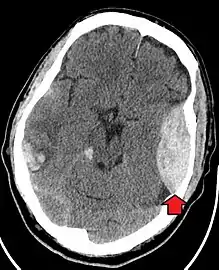

The primary clinical concern with blunt trauma to the head is damage to the brain, although other structures, including the skull, face, orbits, and neck are also at risk.[8] Following assessment of the patient's airway, circulation, and breathing, a cervical collar may be placed if there is suspicion of trauma to the neck. Evaluation of blunt trauma to the head continues with the secondary survey for evidence of cranial trauma, including bruises, contusions, lacerations, and abrasions. In addition to noting external injury, a comprehensive neurologic exam is typically performed to assess for damage to the brain. Depending on the mechanism of injury and examination, a CT scan of the skull and brain may be ordered. This is typically done to assess for blood within the skull, or fracture of the skull bones.[17]

Traumatic brain injury (TBI)

Traumatic brain injury (TBI) is a significant cause of morbidity and mortality and is most commonly caused by falls, motor vehicle crashes, sports- and work-related injuries, and assaults. It is the most common cause of death in patients under the age of 25. TBI is graded from mild to severe, with greater severity correlating with increased morbidity and mortality.[17][18]

Most patients with more severe traumatic brain injury have of a combination of intracranial injuries, which can include diffuse axonal injury, cerebral contusions, and intracranial bleeding, including subarachnoid hemorrhage, subdural hematoma, epidural hematoma, and intraparenchymal hemorrhage.[8][17] The recovery of brain function following a traumatic injury is highly variable and depends upon the specific intracranial injuries that occur, however there is significant correlation between the severity of the initial insult as well as the level of neurologic function during the initial assessment and the level of lasting neurologic deficits.[17] Initial treatment may be targeted at reducing the intracranial pressure if there is concern for swelling or bleeding within this skull, which may require surgery such as a hemicraniectomy, in which part of the skull is removed.[8][17]